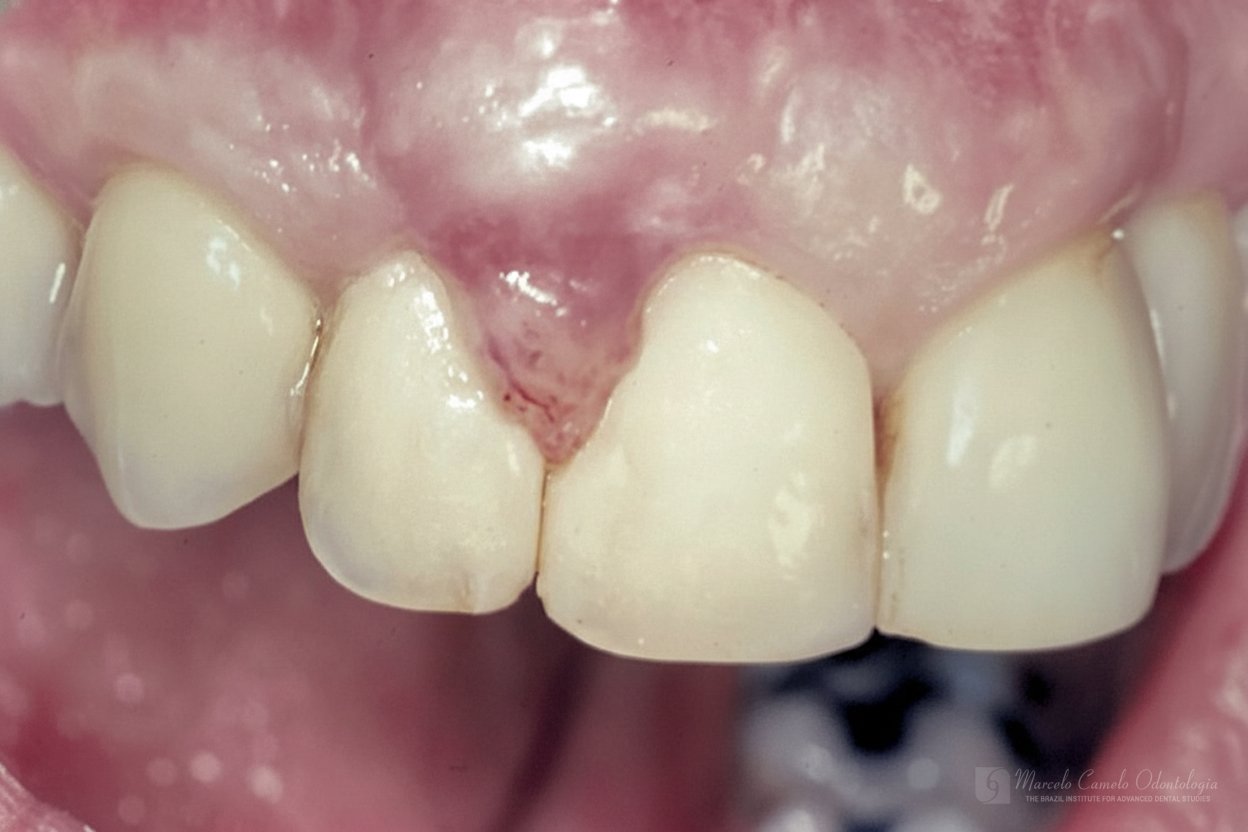

Para casos com boa qualidade de mucosa queratinizada, um envelope vestibular recebe a porção desepitelizada do enxerto pediculado.